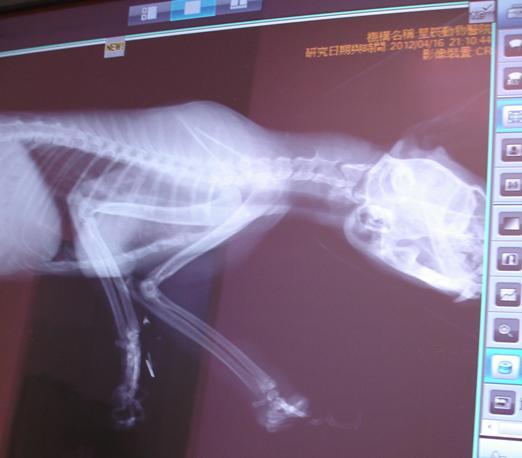

主題: 北科大捕獸夾截肢貓 申請者姓名: 敏大哥 花色: 申請日期: 2012-05-27 17:02:32 申請者部落格: 申請者臉書網址: 所在縣市/合作醫院: 台北市/星辰動物醫院 治療費用: 16200元 需求人數: 38人 已結案 (2013-06-27 13:24:30) 報名人員: Satie Tang(已付款)、李小映(已付款)、Satie Tang(已付款)、謝耶露(已付款)、黃米香(已付款)、Terry Kuo(已付款)、Terry Kuo(已付款)、Terry Kuo(已付款)、Terry Kuo(已付款)、火鳳貍(已付款)、Terry Kuo(已付款)、nene潔(已付款)、Terry Kuo(已付款)、nene潔(已付款)、張小莉(已付款)、Terry Kuo(已付款)、Terry Kuo(已付款)、Susan Chen、LukeC(已付款)、米米玉(已付款)、村田花子(已付款)、Huitzu Wu(已付款)、Yi Hsuan Chen(已付款)、鄭雨農(已付款)、Huitzu Wu(已付款)、Mayhew Chen(已付款)、周欣樺(已付款)、戀星(已付款)、Chia Chun Lin(已付款)、Kyla Chen(已付款)、Cindy Jian(已付款)、Ariel(已付款)、Frida Chen(已付款)、Kristy Lee(已付款)、Lai Fhifhi(已付款)、蔡勝鴻(已付款)、Kristy Lee(已付款)、Dolphin(已付款)、Li Li Hsieh、Aidan Shih(已付款)、 候補人員: Judy Meow、小節、Ivana Wen、WeiLin Chen、 動物病情說明: 4/16晚上6:30左右,民眾通報請支持流浪貓TNR計劃協會,在八德路二段北科大附近發現一隻捕獸夾貓咪急需誘捕. 由協會派本人處理. 當天誘捕到緊急送至星辰動物醫院.

吳醫師研判應已受傷數日,嚴重脫水. 左前肢已確定掌骨被捕獸夾夾傷 導致開放性骨折,肌肉組織分離. 目前僅剩骨頭與捕獸夾相連. 拍攝X光後評估截肢至腕骨. (有保留小肉墊,這樣行動時有緩衝,底部不容易磨破皮.)